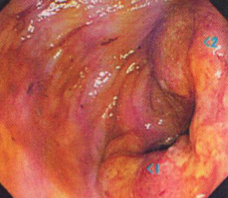

大腸がんは下のような大腸造影検査(注腸検査)、大腸カメラ(大腸内視鏡検査)にて発見、確認することができます。病変の場所、進行の程度により、腸を切る場所や範囲が変わってきます。

S状結腸という場所にできた大腸がんです。がんのために、腸が狭くなっています

肛門から約5cmの位置に出来た大腸がん(直腸癌)です。このような肛門に近いがんも、条件がそろえば人工肛門は作らずに腹腔鏡下に手術することが可能です。